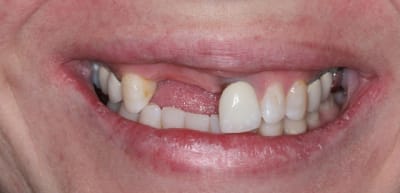

On avance dans le cas, j'ai revu la patiente hier.

Elle est satisfaite et moi pas vraiment, comme quoi...

Elle ne veut pas faire de chir mucco gingivale et accepte éventuellement que je fasse une petite chir d'élongation coronaire sur 21 car elle trouve cela surperflux.

Tristesse et difficulté des sourires gingivaux !

J'avais bien raison de me méfier au départ...

Dommage pour la teinte...

Une greffe osseuse aurait bcp aider, les implants sont trop enfouis par rapport à la 21.

Je suis persuadé que si ton prothèsiste réussit à reproduire la richesse des petits défauts de ses propres dents sur tes dents en céramique , ce serait et ça passerait bcp mieux

Je crois que finalement ces trois trop jaune et quasi monolithique ds leur couleur est vraiment la chose la plus atroce

Bon finalement je vous poste le cas terminé.

La prochaine fois je ferrai une greffe d'apposition comme j'avais pu le préssentir... Ca me permettra de garder les papilles.

A la prochaine séance je gomme la coloration mésiale de 12, c'est promis ;+)

Un cas pas évident... l'important est que la patiente soit contente à la fin.

Mon DuDule quel dommage que tu n'ai pas un ditramax car ta ligne interincisive n'est pas parallèle au plan médian et la ligne des bords libres pas parallèle à la ligne blanche masquant les yeux!